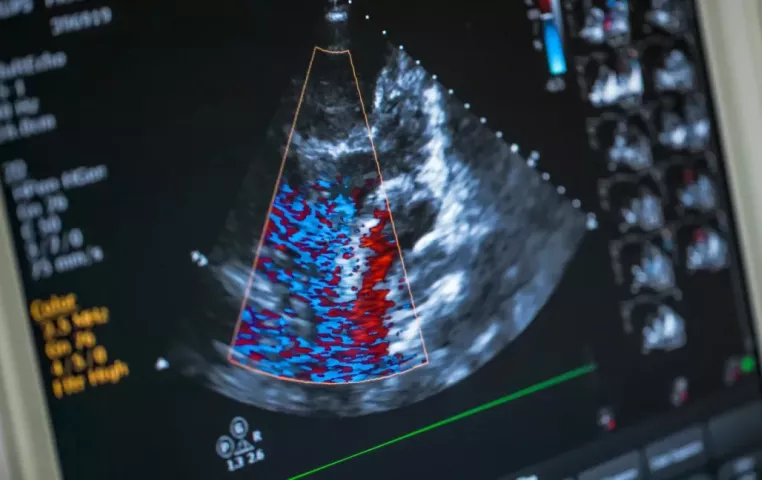

Échographie cardiaque

Échocardiographie

L’échographie cardiaque utilise des ultrasons pour produire des images détaillées de la structure et du fonctionnement du cœur. Elle permet d’évaluer la force du muscle cardiaque, le fonctionnement des valves et de détecter une insuffisance cardiaque, une maladie valvulaire ou des anomalies congénitales — sans rayonnement.